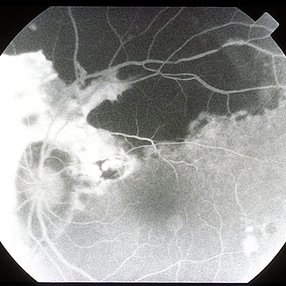

Subretinal Hemorrhage 4

Mar 14 2013 by Maurice F. Rabb

A 59-year-old black woman with an extensive progression of the hemorrhage around the superior margin of the disc and extending toward the macula. A barrier of laser was applied on the foveal margin of the hemorrhage. The hemorrhage remained stable with vision of 20/20.

Condition/keywords: 20/20, foveal margin, subretinal hemorrhage, superior margin of the disc